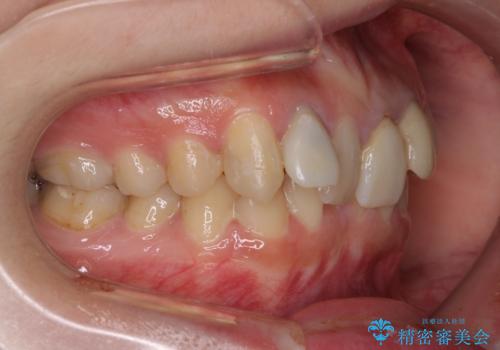

- 前歯のデコボコと、その結果むし歯が進行していることを気にして来院された患者様です。

前歯や奥歯の根管治療を行い、その後上下左右の第一小臼歯4本を抜歯してワイヤー装置にて矯正治療を行うこととしました。

矯正治療後には、根管治療を行った歯をオールセラミッククラウンにて補綴治療を行うこととしました。